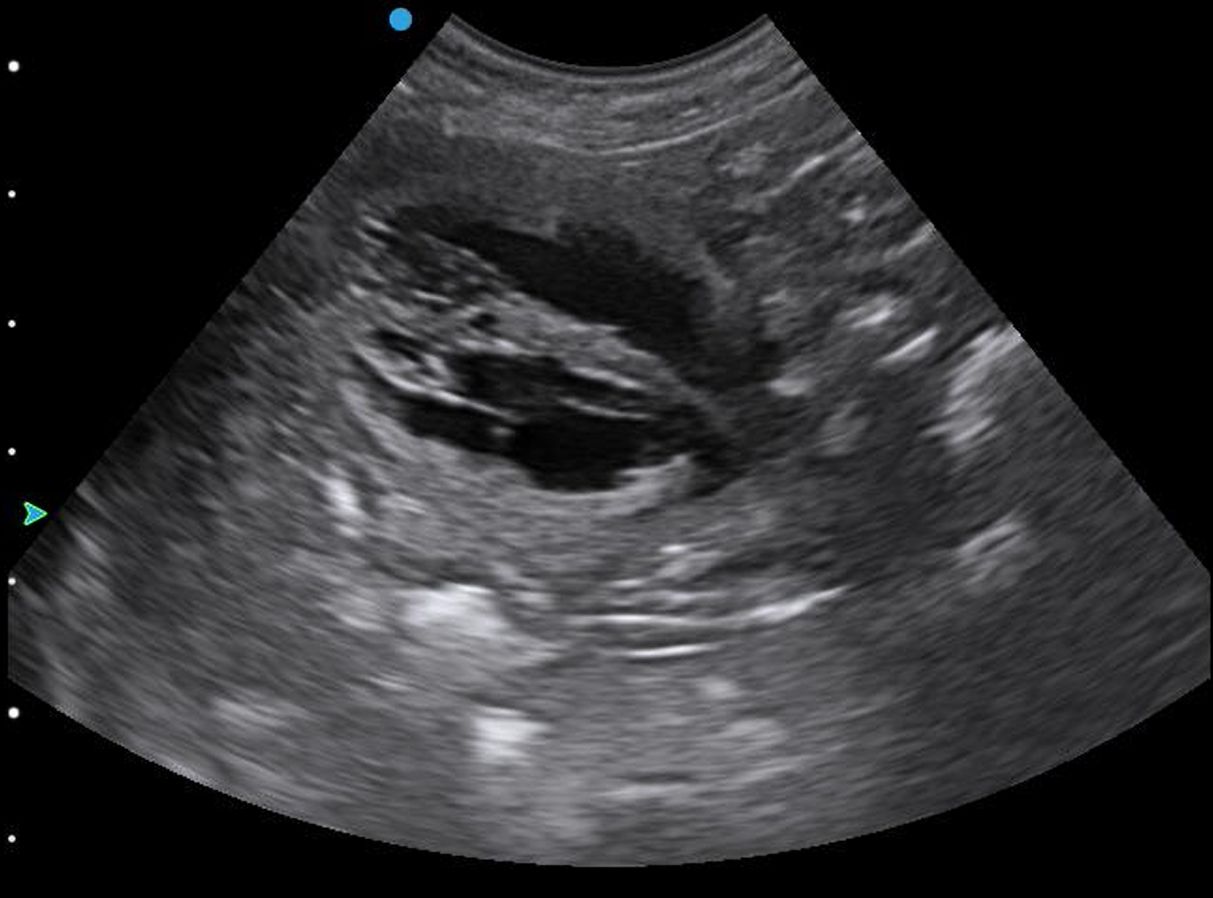

Scan from my Apogee Lite, I can take photos on machine & videos which of course can be sent to my clients.